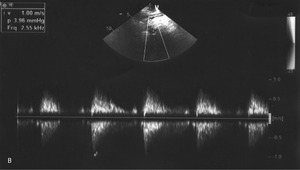

W badaniu przedmiotowym zwracał uwagę brak tętna na lewej tętnicy promieniowej, słabo wyczuwalne tętno na lewej tętnicy łokciowej oraz cichy szmer skurczowy w prawej okolicy podobojczykowej słyszalny na obszarze wielkości dłoni. Tętno na kończynach dolnych było dobrze wyczuwalne, symetryczne. Ciśnienie tętnicze zmierzone na lewym ramieniu wynosiło 110/70 mmHg, na prawym ramieniu 190/110 mmHg. W echokardiogramie poza granicznie przerośniętą przegrodą międzykomorową nie stwierdzono istotnej patologii. Wymiar aorty wstępującej, zastawki serca, przepływy w naczyniach odchodzących od łuku aorty oraz w aorcie zstępującej były prawidłowe (ryc. 1).